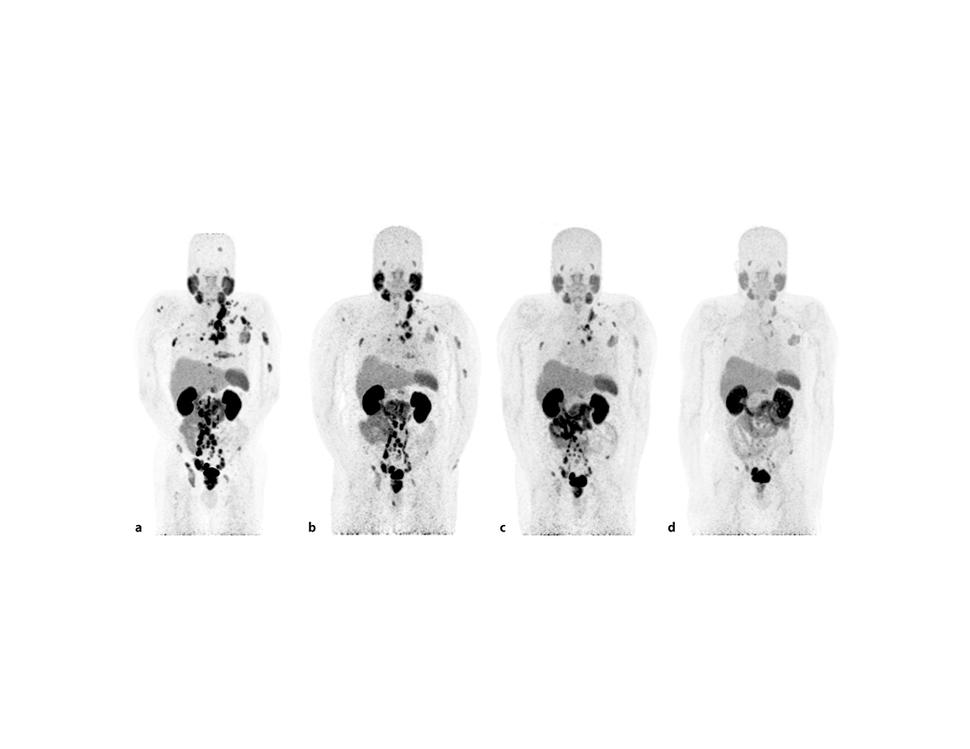

图片来源:National Cancer Institute(NCI),PSMA PET 扫描可在传统骨扫描之前发现更微小的前列腺癌转移灶,这也是美国前列腺癌晚期治疗中越来越核心的影像工具。

从临床策略上看,美国目前最大的优势之一,是将PSMA PET分子影像提前用于治疗决策,而不仅仅用于复发确认。2026年U.S. Food and Drug Administration批准的新一代 Pylarify TruVu 成像系统,使PSMA扫描产能提高约50%,这意味着更多患者能在更早阶段发现微小转移灶,而不是等到传统骨扫描已经出现明显病灶时才调整方案。

接受 Pluvicto(177Lu-PSMA-617)治疗后,PSMA显像中的肿瘤负荷可明显下降。该疗法已成为美国治疗晚期前列腺癌的重要新路径。(图片来源:Diagnostic Imaging / FDA 临床资料)